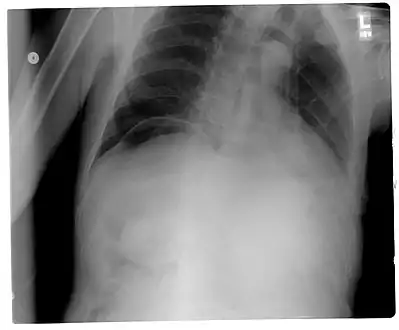

Frontal chest X-ray. The air bubble below the right hemidiaphragm (on the left of the image) is a pneumoperitoneum.